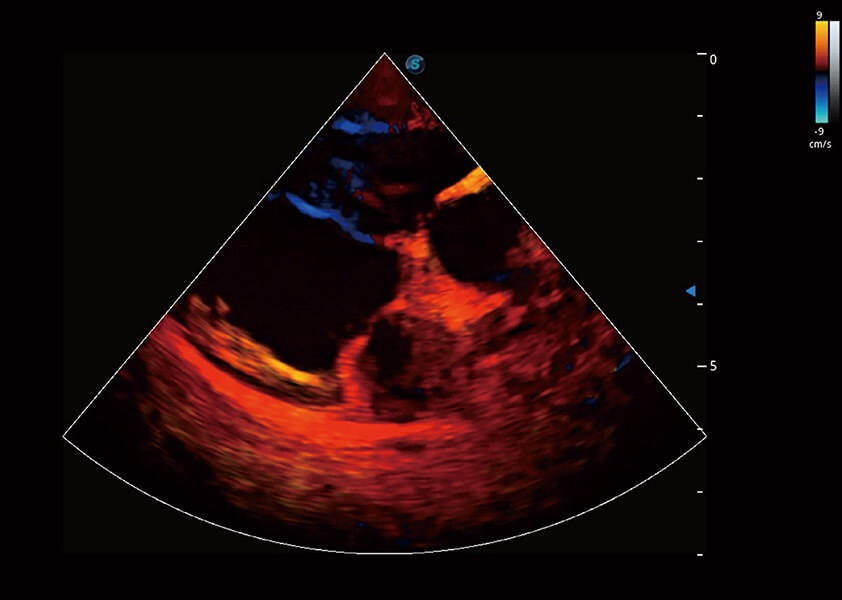

优异的基础图像

(犬)四腔心血流

心脏解决方案

ProPet 60 配备了丰富的心脏探头群、先进的成像技术和专业的心脏测量工具,可帮助动物医生为不同体型和生理结构的动物提供心脏和心肌功能的全面评估。

• TDI 组织多普勒成像

实时用颜色表示心肌组织运动,观察和定量组织的运动情况,对快速检测与评估心肌的灌注和活性、电传导及心肌收缩和舒张功能等均能提供重要的诊断信息。